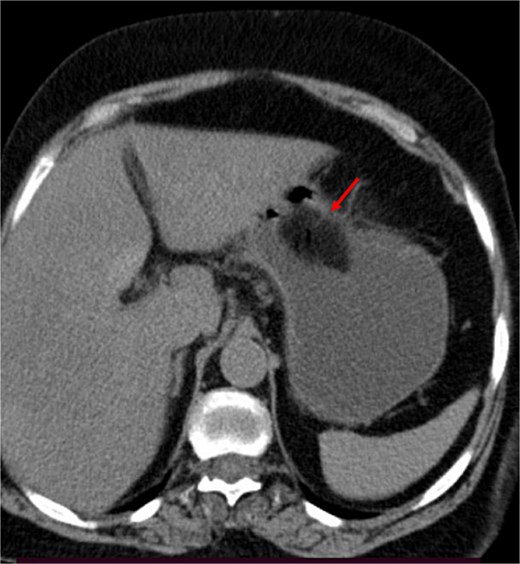

A contrast-enhanced CT of the abdomen was performed and revealed an intraluminal mass in the pylorus causing gastric dilatation (Fig. 1) and another intraluminal mass in the terminal ileum causing small bowel dilatation (Fig. 2). A nasogastric tube was inserted, and the patient was taken for exploratory laparotomy. There were significant gastric and small bowel dilatations; a gastrostomy and enterostomy were performed, and two foreign bodies were extracted (Fig. 3). The incision sites were then repaired.

The arrow indicates an intraluminal mass in the small bowel causing proximal small intestinal obstruction.